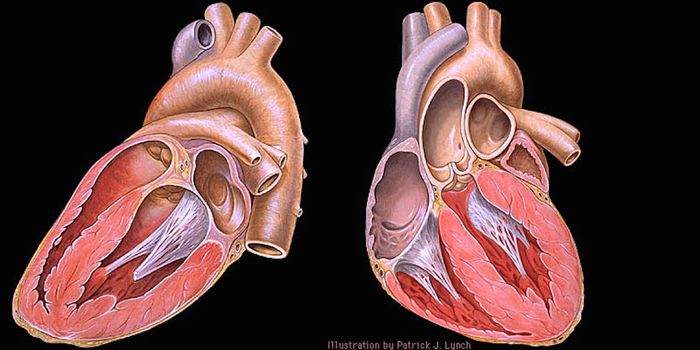

JUL 07, 2016CardiologyWhether you let it all out or bottle it up, arguments between spouses align with specific health problems, report resear ...